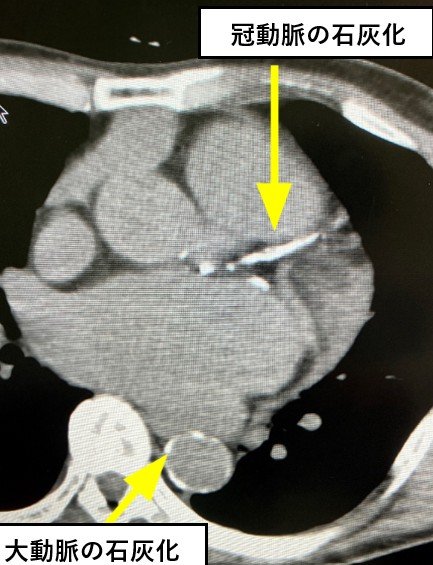

さて、突然死を防ぐ検査として前回、胸部レントゲン検査を行うと、大動脈解離や心疾患、脳卒中の発症リスクが高まる「大動脈石灰化」を見つけられることがあるとお伝えしました。

高血圧症や脂質異常症、糖尿病などの動脈硬化の危険因子をもつ人は、健康診断や人間ドックの際に胸部レントゲン検査の撮影を「正面」と「側面」の2方向でしてもらうといいでしょう。

ちなみにオプションでCTをつければ、狭心症に関係する冠動